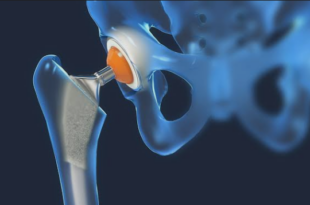

Read More »Total Hip Replacement in Chandigarh – Expert Surgery for Pain-Free Living

Hip pain can really affect your life. It can stop you from walking, sitting or doing things you normally do. When medicines and physiotherapy do not work, Total Hip Replacement in Chandigarh is a solution. Zubin Ortho is a trusted name for care. They use surgical techniques and personalized treatment …

Read More »Hip Replacement Surgery in Chandigarh – Advanced Care for Pain-Free Mobility

Hip pain can have a major impact on your mobility and quality of life. Even simple, mundane acts such as walking, going up and down stairs or sitting comfortably may become challenging with time. However, when medicines and therapies don’t help out effectively then Hip Replacement Surgery in Chandigarh is …